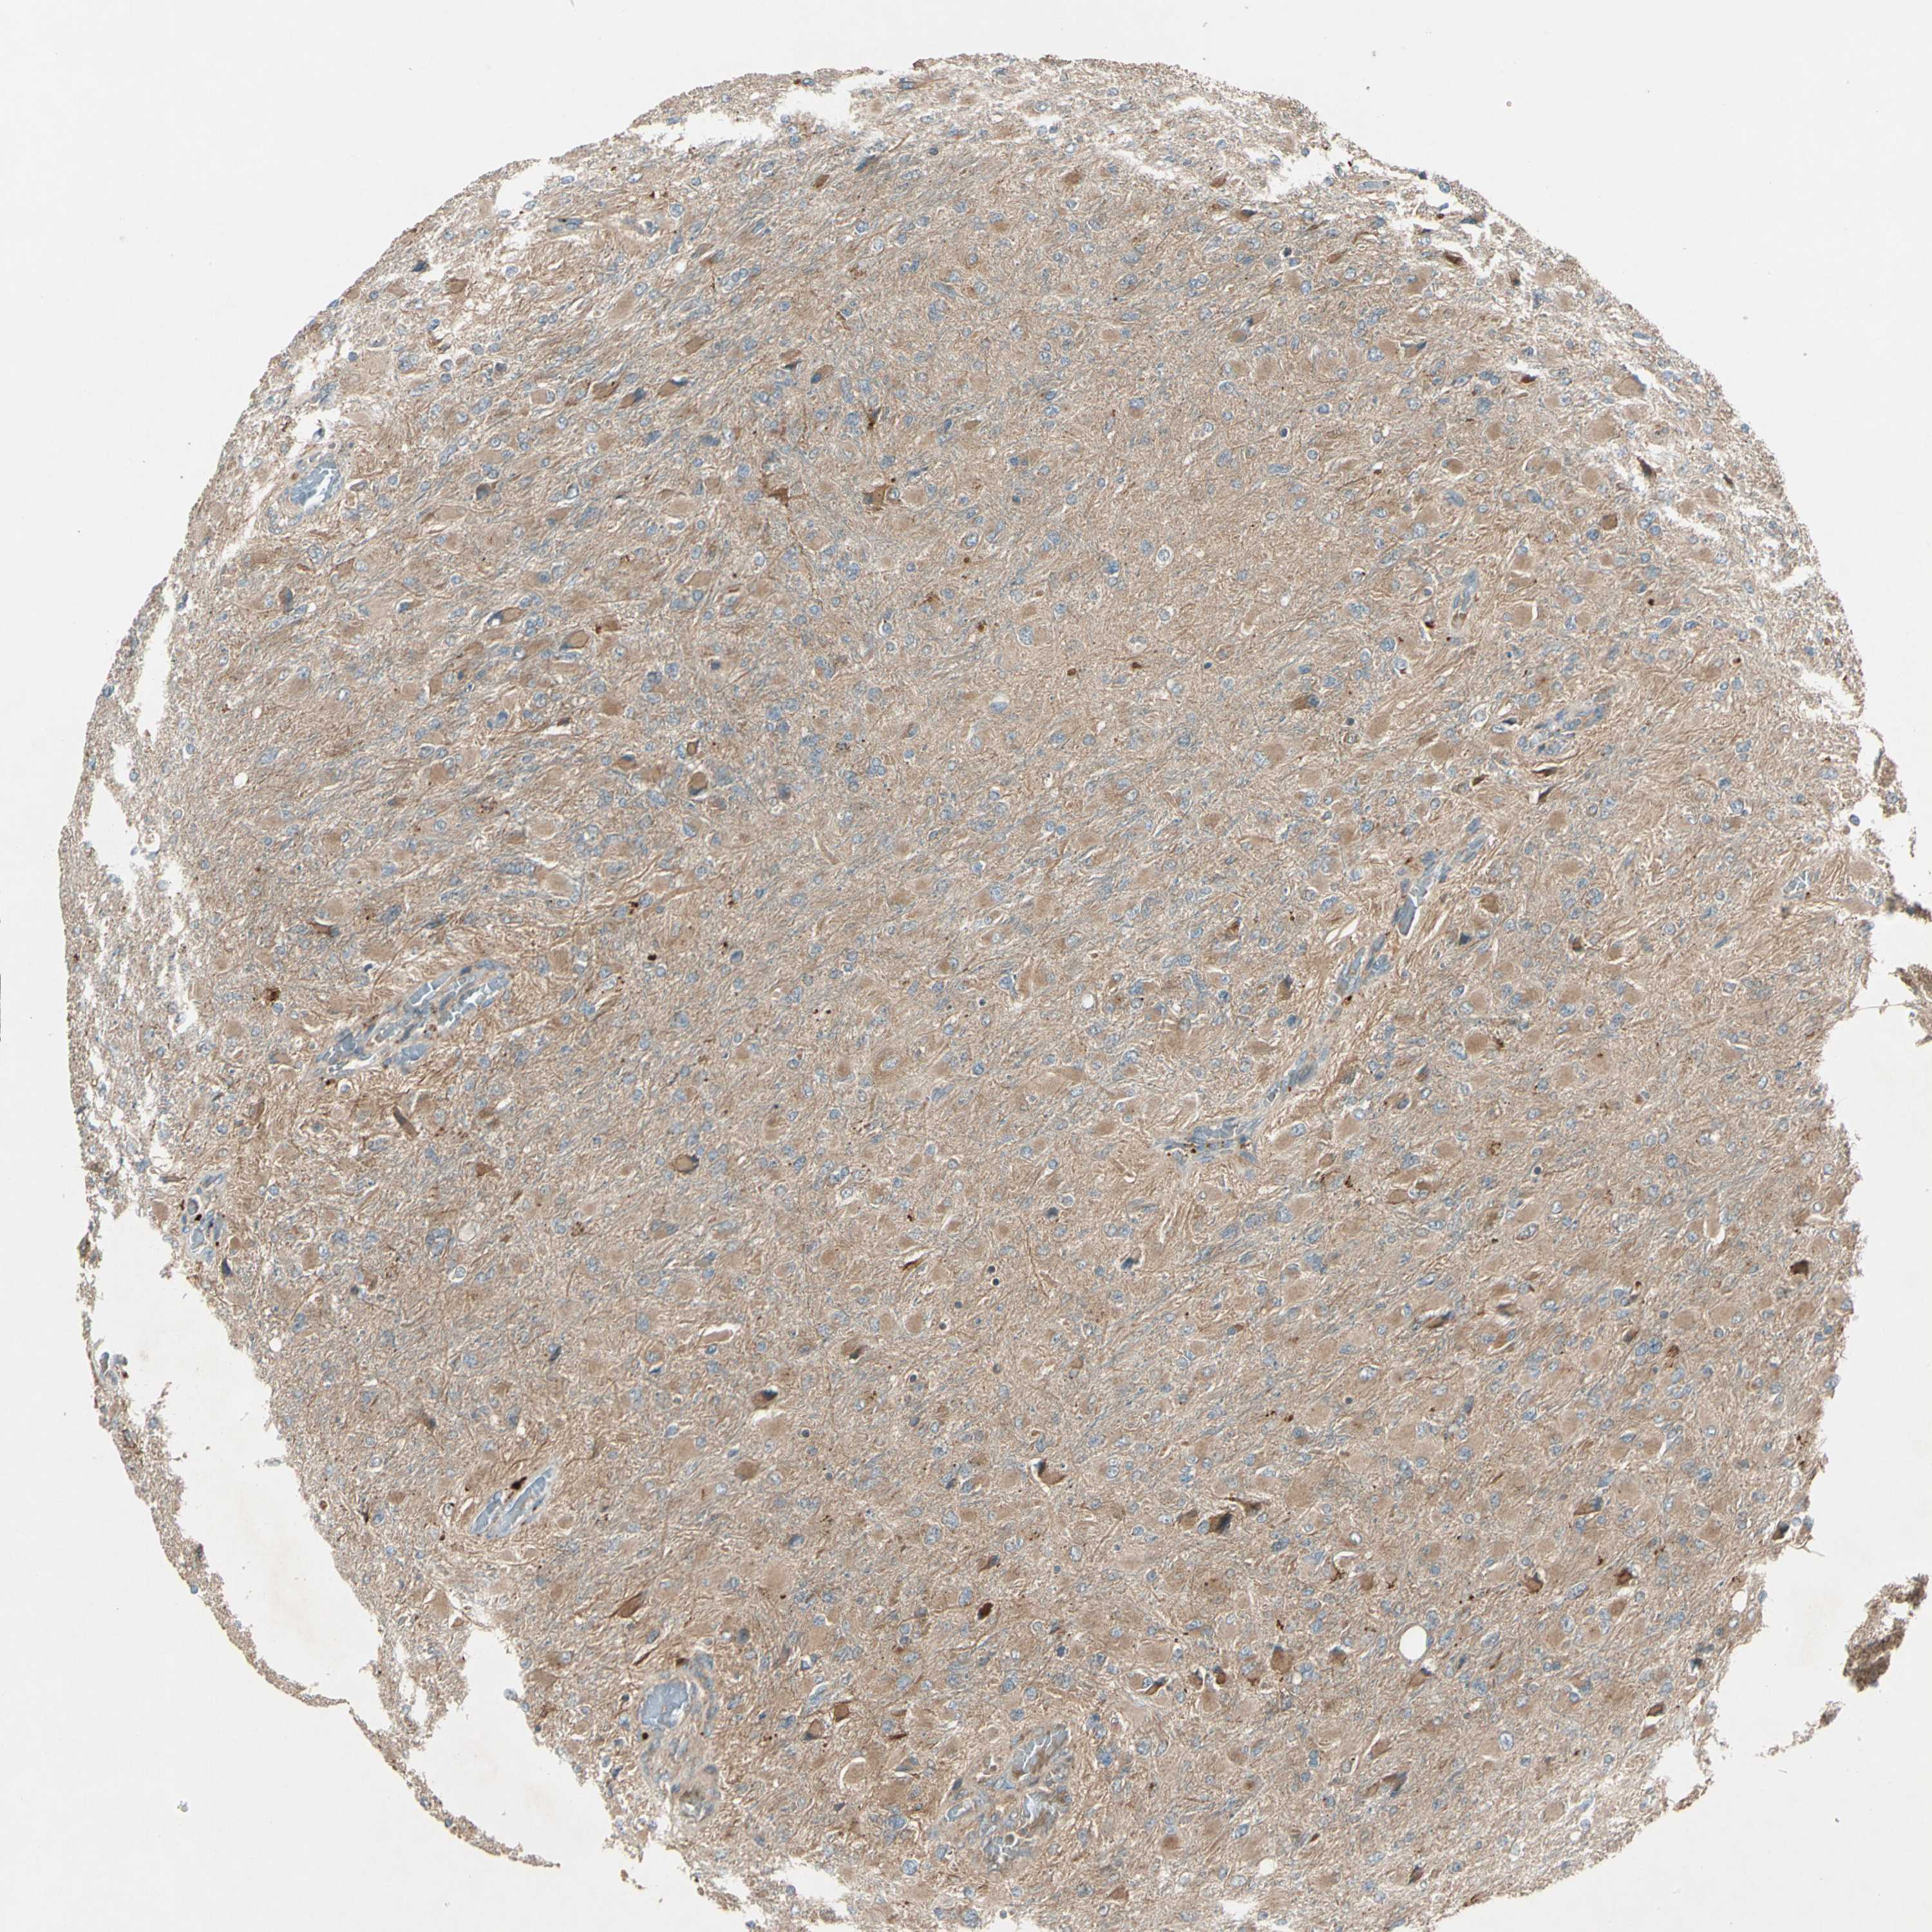

GLIOMA - Protein expressioni

A mouse-over function shows sample information and annotation data. Click on an image to view it in a full screen mode. Samples can be filtered based on level of antibody staining by selecting one or several of the following categories: high, medium, low and not detected. The assay and annotation is described here.

Note that samples used for immunohistochemistry by the Human Protein Atlas do not correspond to samples in the TCGA dataset.

Antibody stainingi

Antibody staining in the annotated cell types in the current human tissue is reported as not detected, low, medium, or high, based on conventional immunohistochemistry profiling in selected tissues. This score is based on the combination of the staining intensity and fraction of stained cells.

Each image is clickable and will lead to virtual microscopy that enables deeper exploration of all samples and also displays staining intensity scores, fraction scores and subcellular localization as well as patient and tissue information for each sample.

Antibody HPA007982

Antibody HPA011933

Staining

High

Medium

Low

Not detected

Intensity

Strong

Moderate

Weak

Negative

Quantity

>75%

75%-25%

<25%

None

Location

Nuclear

Cytoplasmic/membranous

Cytoplasmic/membranous,nuclear

Glioma, malignant, High grade

Glioma, malignant, Low grade